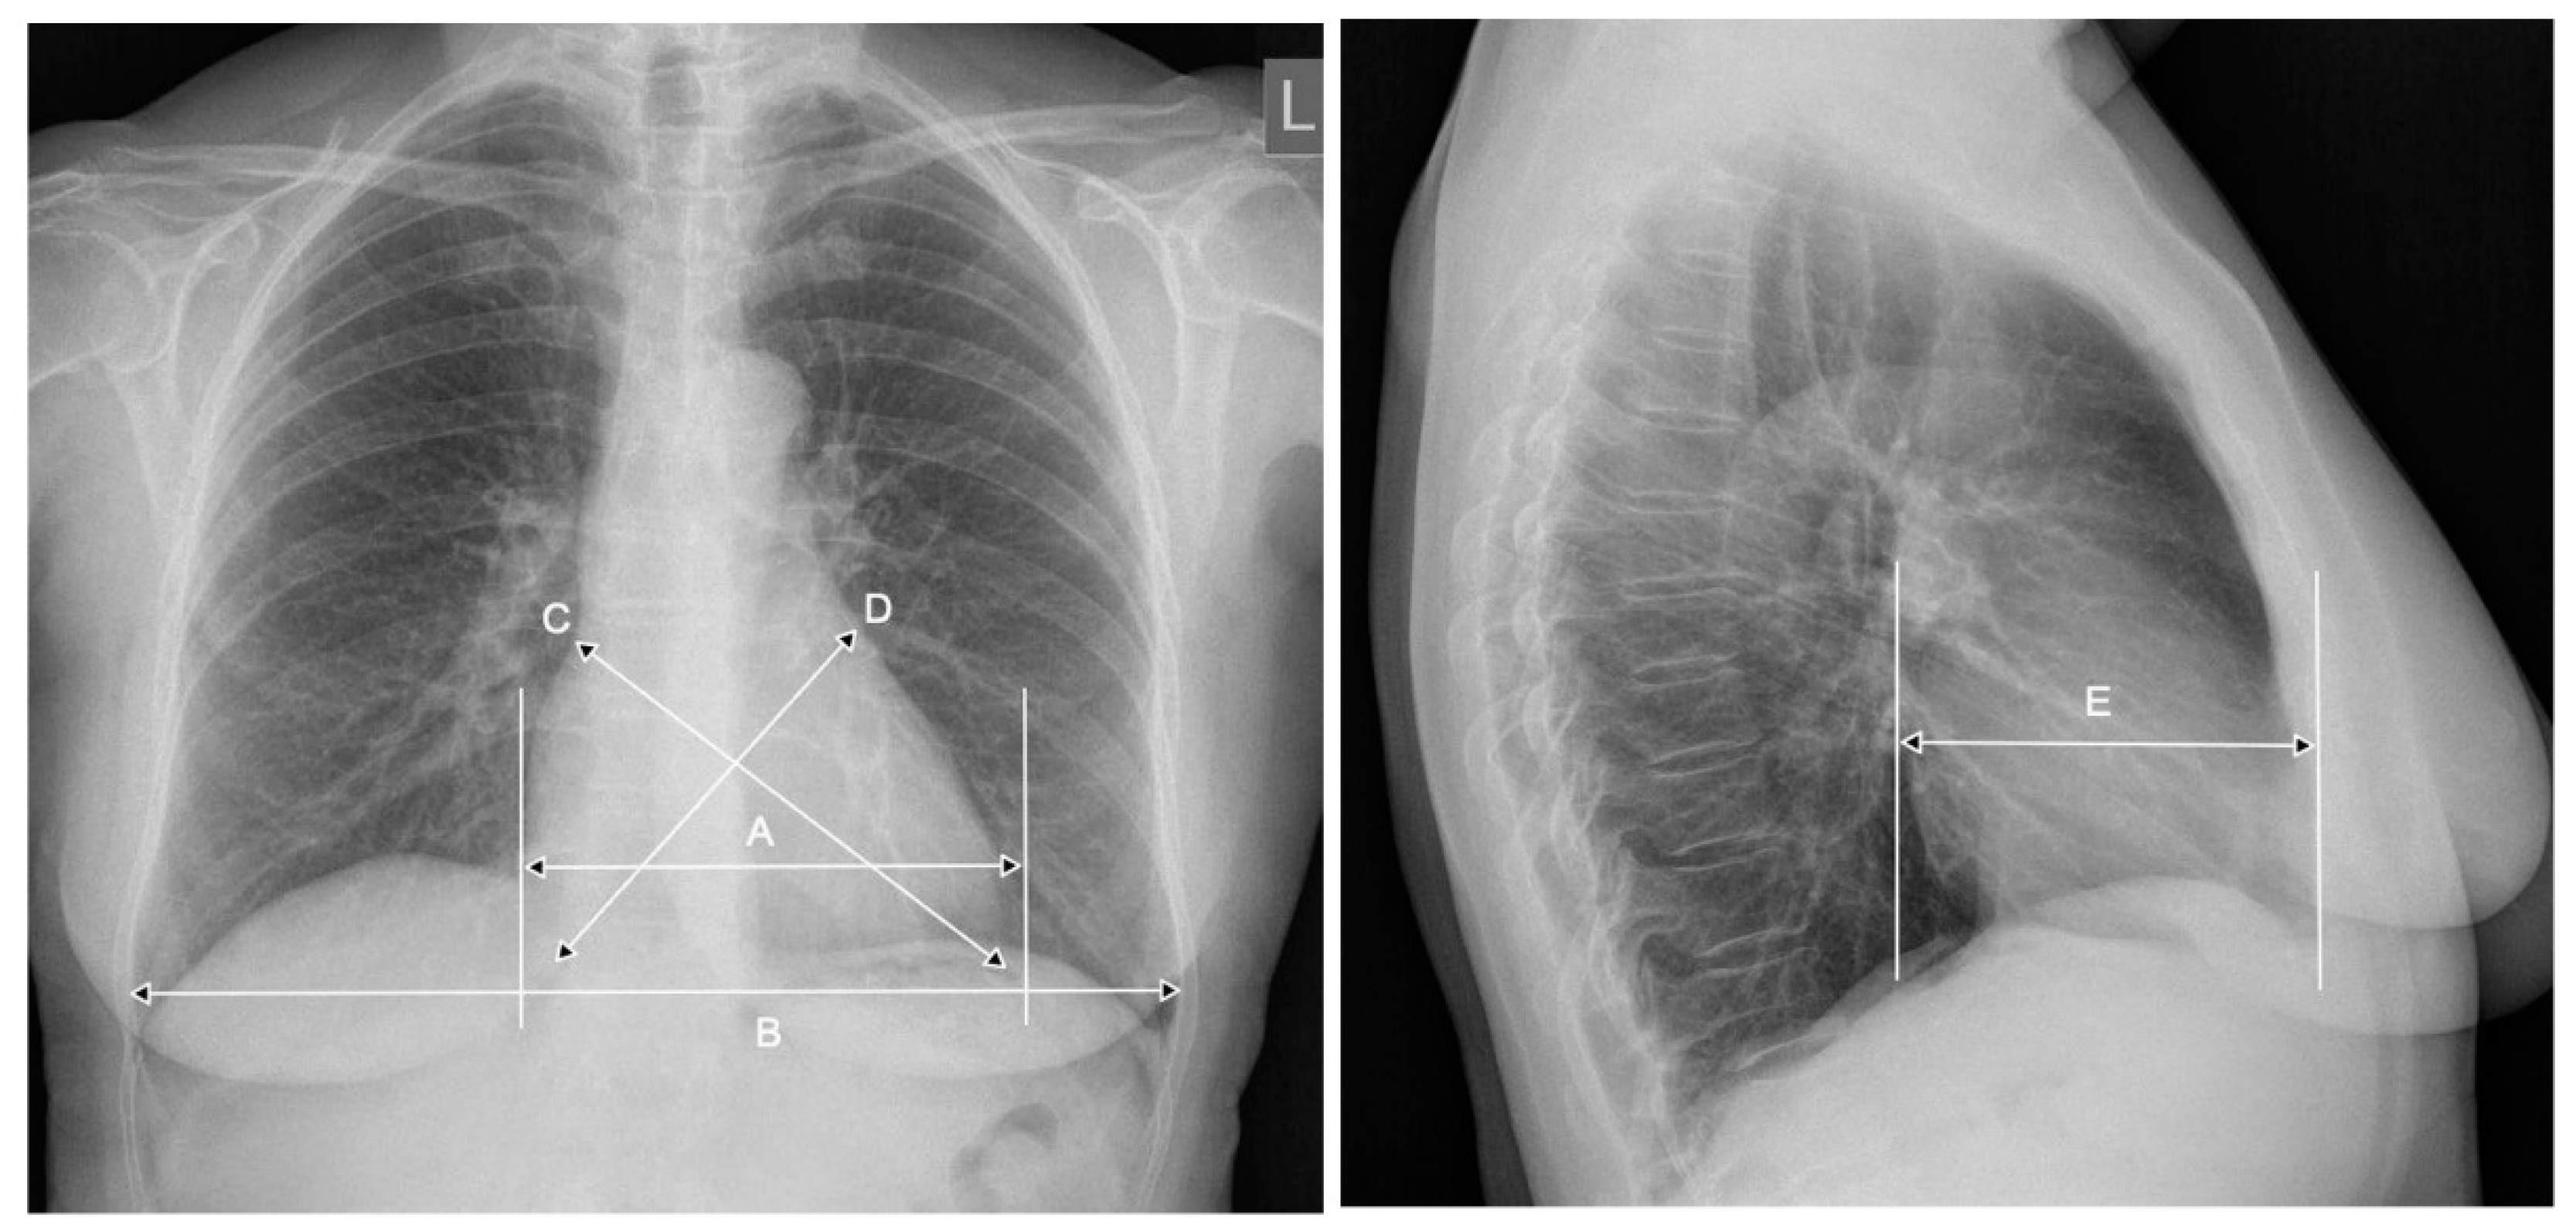

2. CTR—The Importance of Radiograph Projection